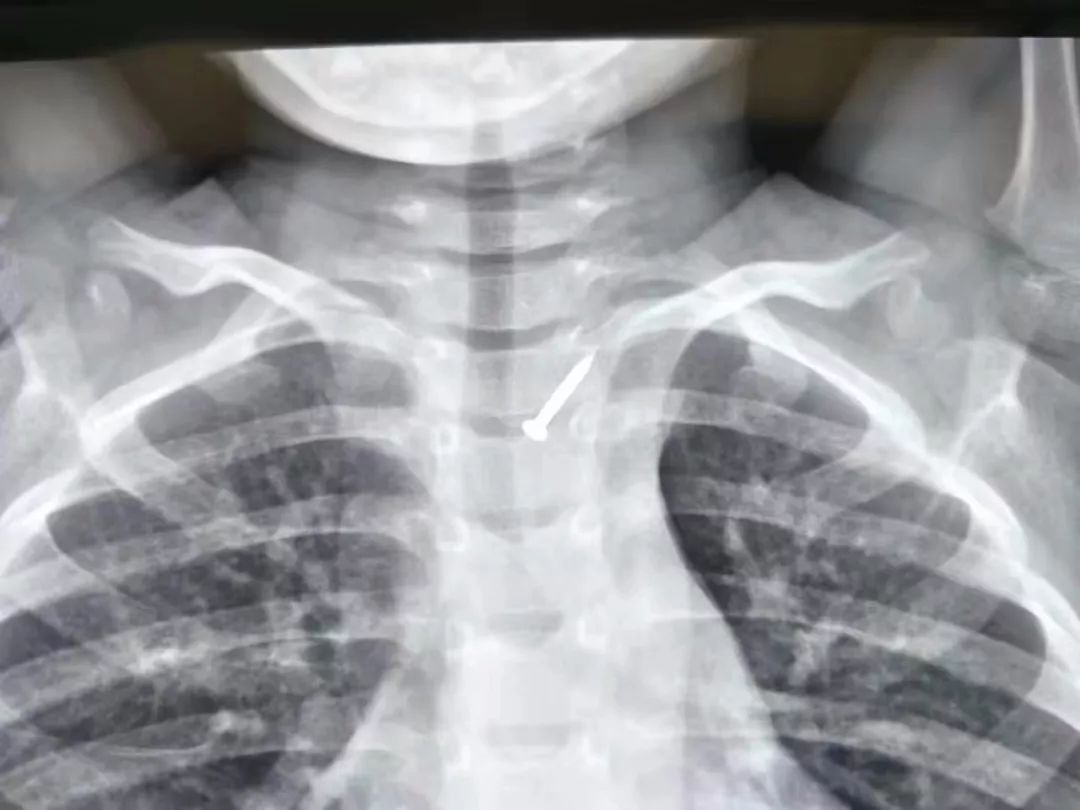

原来,4岁男孩小齐下午在幼儿园玩耍时,不知怎么地找到一枚“网线钉”,出于好奇,把“网线钉”吞进口中,一咕噜,咽进了食道。幼儿园老师发现后,立刻通知家长。当地医院拍片结果显示,网线钉位置已经嵌入食道,相当凶险,建议立刻转院!

(网线钉嵌入食道)